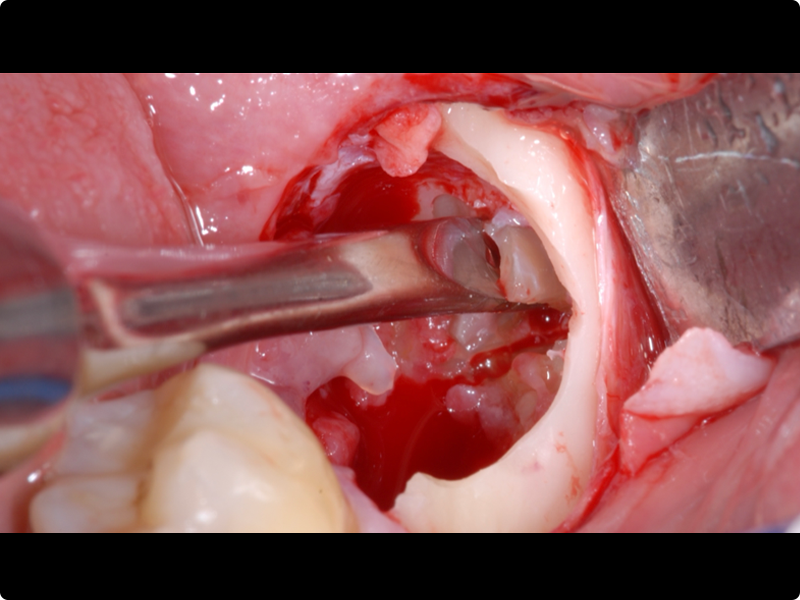

- Odontotomy and rhizotomy.

- Dislocation and extraction.